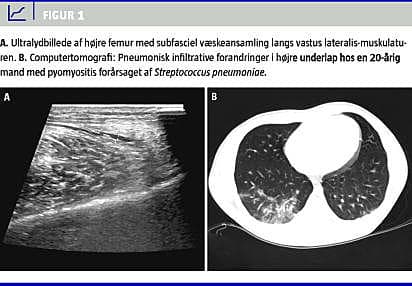

Objektivt var patienten højfebril (39,9 °C) og alment påvirket. Ved hjerte- og lungestetoskopi fandt man normale forhold. Højre femur var hævet og spændt, distalt og lateralt var der et ca. 10 × 15 cm stort område, hvor huden var ødematøs, rød og varm. Der var udtalt ømhed af muskulaturen ved palpation, men ingen fluktuation eller krepitation. Der var ingen hævelse eller rødme omkring knæleddet og ingen intraartikulær ansamling. Paraklinisk var C-reaktivt protein (CRP) 265 mg/l (referenceværdi: < 8 mg/l), og leukocyttallet var 17,8 mia./l (referenceværdi: 3,5-10,0 mia./l). En ultralydskanning viste væskeansamling langs vastus lateralis-muskulaturen (Figur 1 A).

På mistanke om nekrotiserende fasciitis blev der foretaget akut fasciotomi. Ved indgrebet blev der fundet normale forhold i subcutis og fascie, men overfladiske nekrotiske områder i vastus lateralis-muskulaturen. Nekroserne blev excideret og sendt til mikro-biologisk undersøgelse, og der blev indledt behandling med intravenøst givet meropenem, ciprofloxacin og clindamycin. I andet indlæggelsesdøgn blev der i vævsbiopsierne fundet vækst af S. pneumoniae , der var følsøm for penicillin og clindamycin. Bloddyrkninger var uden vækst. Røntgen af thorax viste tegn på et infiltrat basalt i højre lunge, hvilket blev bekræftet ved en efterfølgende computertomografi af thorax og abdomen (Figur 1B). Der blev desuden foretaget en ekkokardiografi, der viste normale forhold. Paraklinisk blev der fundet normale immunglobulinkoncentrationer og en negativ hiv-test.